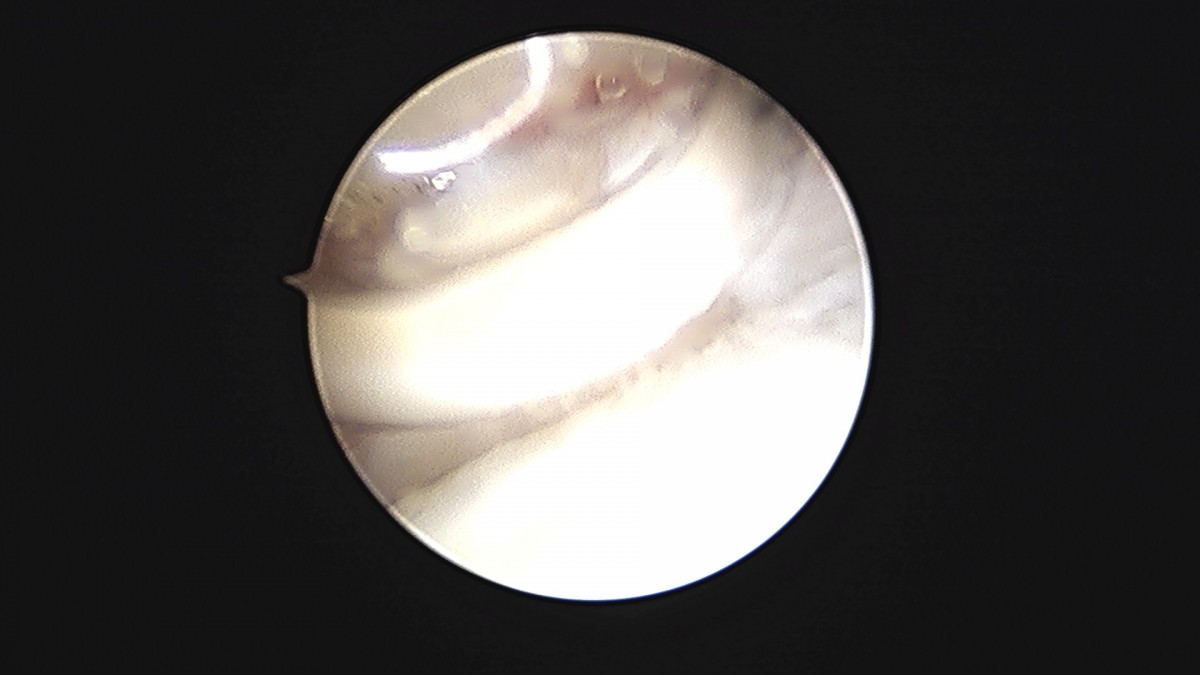

이재상원장님 발목 연골병변 제거술 및 골수 자극술 장경O 환자

작성자 최고관리자 댓글 0건 조회 375회 작성일 25-09-16 16:14